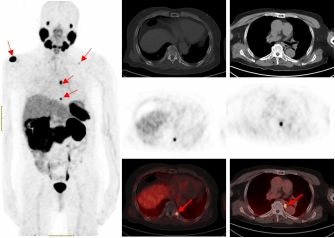

一名75的岁男性患者自2019年确诊前列腺癌后,先后接受过两次内分泌治疗及前列腺癌根治术的综合治疗。在术后两年的复查中发现血PSA持续升高,CT检查和全身骨显像检查均未发现明显异常,医生建议随诊,患者来到91制片

附属医院要求进一步检查。经核医学科68Ga-PSMA PET/CT检查后结果显示,双侧肩胛骨、左侧第9后肋、第2腰椎及纵隔淋巴结均已存在癌症转移。